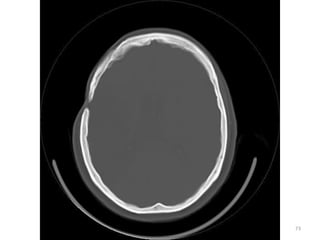

CORTES FOSSA POSTERIOR

SUPRA TENTORIAL

IMAGENS ÓSSEAS